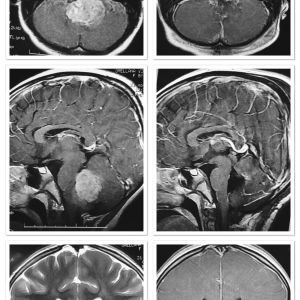

MEDULOBLASTOMA

DESCRIPCIÓN